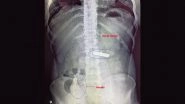

Delhi: Doctors Remove Shaving Razor From Man’s Stomach As He Swallows It After Quarrel With His Father